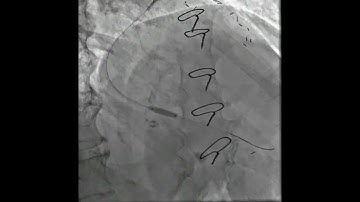

Decoding CTO Case - 7 | CTO PCI In Post - CABG By Dr. Sharath Reddy